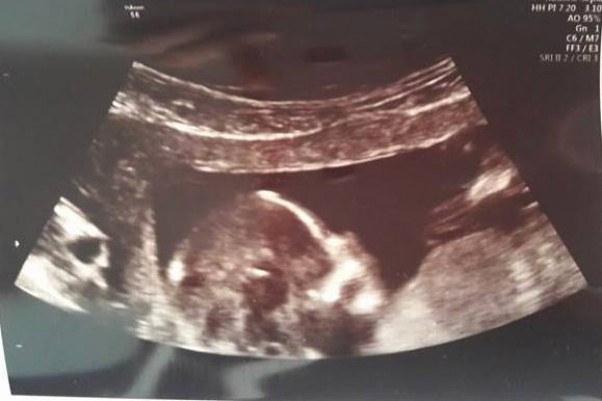

14 tydz 5 dzień, trochę niewyraźne te zdjęcia z USG ale widać tu buźkę i nosek malutki <3